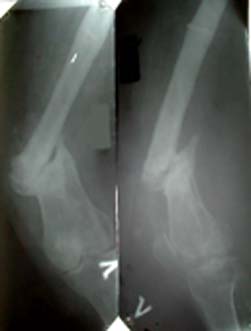

Глубокоуважаемые коллеги.Просьба оказать консультационную помощь Женщина 40 лет. ДТП в 1996: открытый перелом левого бедра, мыщелковый правой голени.

В настоящее время укорочение левой н/конечности 4 см, объем движений левого колена до 70 градусов, патологическая подвижность в области перелома. Планируем дистракцию с помощью аппарата до выравнивания с длиной правой конечности, а вторым этапом резекцию концов отломков бедра и остеосинтез штифтом через интеркондиллярную вырезку.Остеотомию правой б/б кости. Резецированные участки возможно пойдут на заполнение остеотомированной зоны б/берцовой кости. Вопросы по правильности такого планирования, по компоновке аппарата (темп дистракции, жесткость фиксации дистального отломка).Максимов Б.Ю.Сердобск, Пензенская обл.

Резекция здесь - это укорочение, так что лучше подумать, может, о костной пластике? Нельзя ли прислать снимки с чуть большим разрешением?

Безусловно, снимок слабоват, спешил... Но резекция, по моему, не даст укорочения,

так как имеется остеоидная ткань и довольно значительная на торцевых поверхностях отломков.